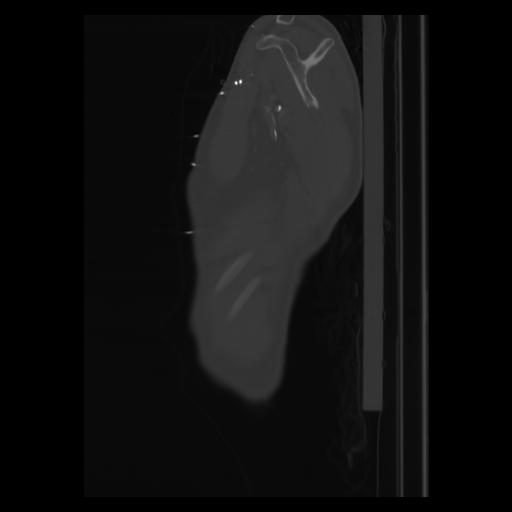

30 CUERPO,CE,Sagittal,3.000,CUERPO,Sagittal,